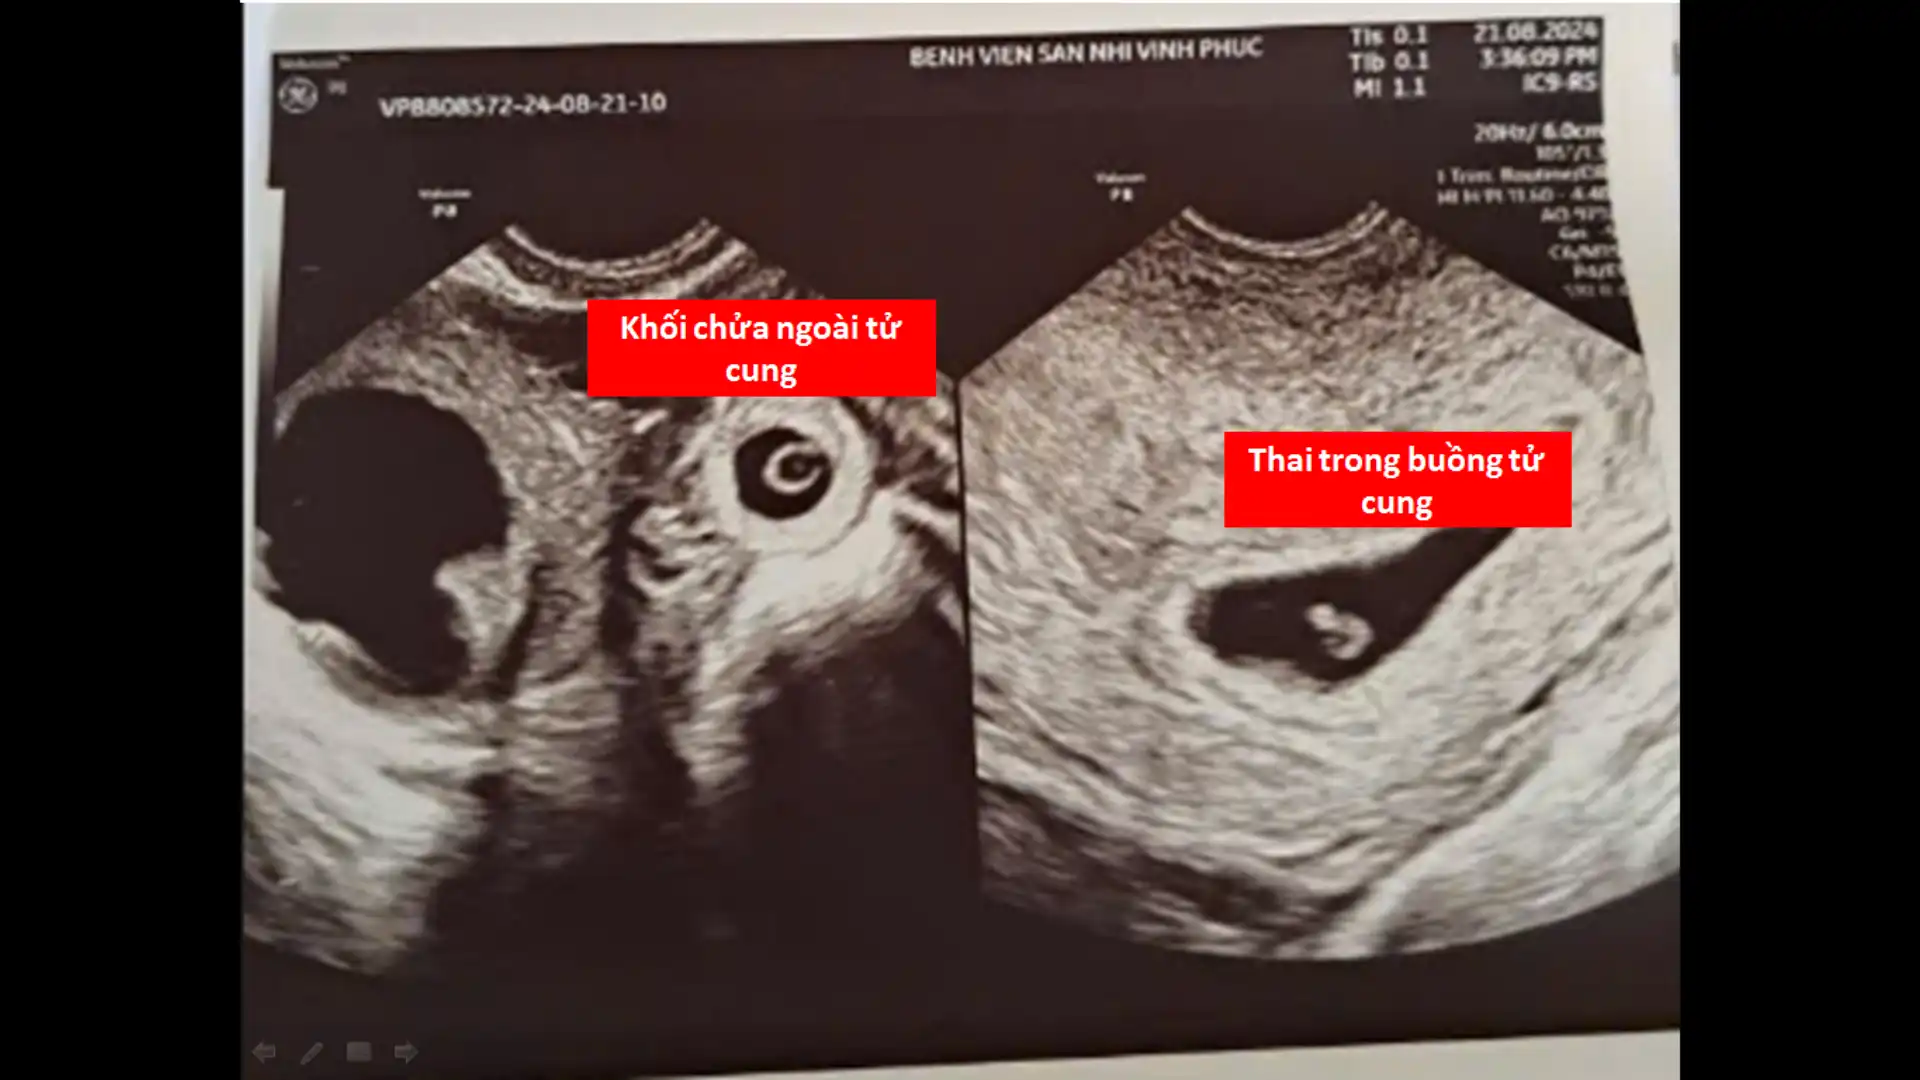

Hình ảnh siêu âm lúc vào viện: song thai khác vị trí với 01 thai trong buồng tử cung và 01 thai ngoài buồng tử cung.

Sản phụ nhập viện khi thai khoảng 5 tuần với triệu chứng đau bụng. Qua thăm khám lâm sàng và siêu âm, bác sĩ phát hiện:

Một thai nằm trong buồng tử cung

Đồng thời có một thai ngoài buồng tử cung, vị trí vòi tử cung bên phải